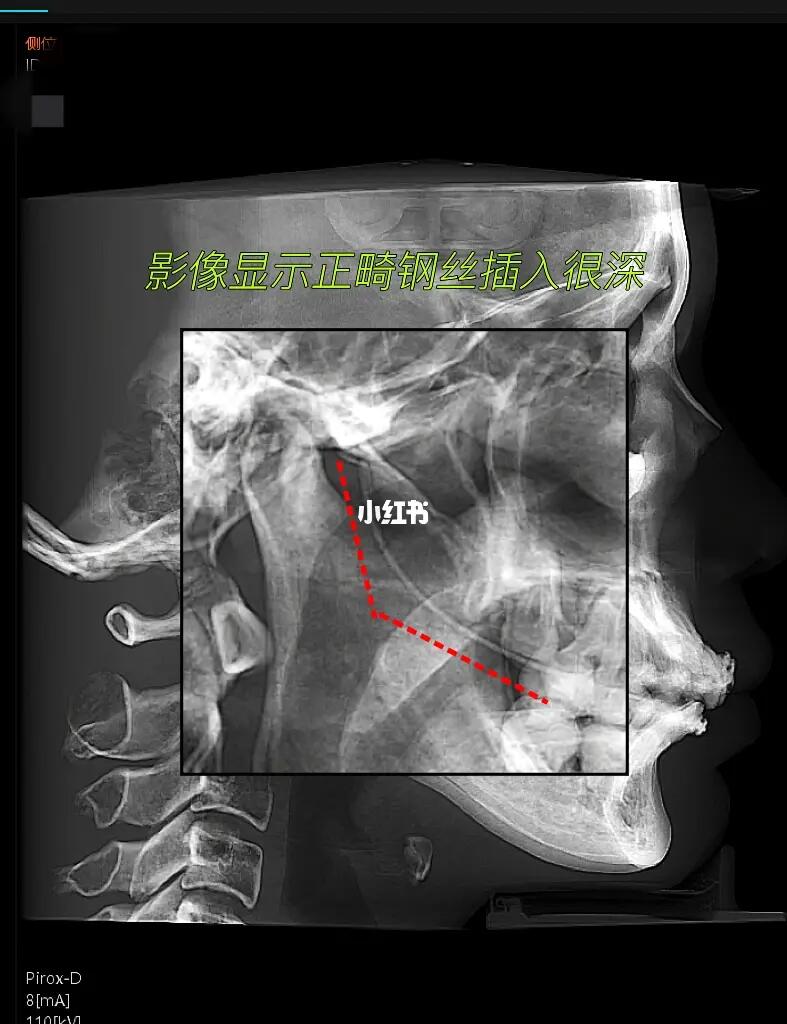

[惊恐R]通过拍片发现,上颌牙的正畸钢丝越过翼静脉丛都快插进颅内了[惊恐R]都靠近脑膜中动脉了,这要是再深一点或者偏一些[惊恐R]刺破了血管,后果不堪设想!